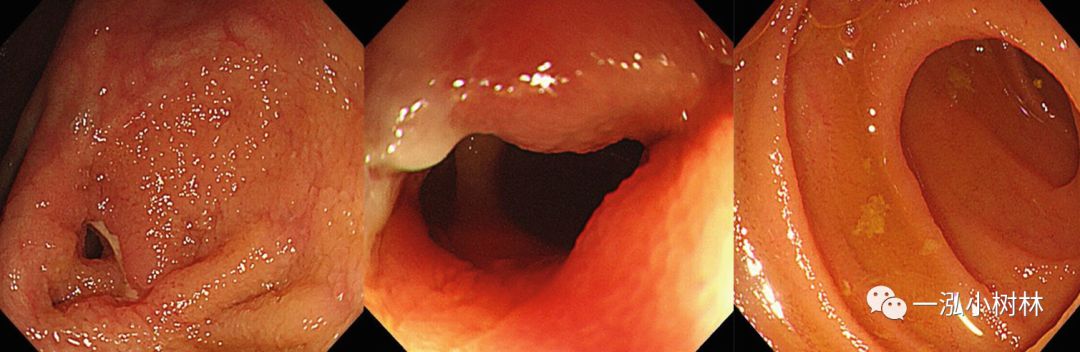

随着高清晰度白光内镜或高分辨率内镜(HRE)应用以来,增加了结肠息肉的检出率。高清白光内镜产生的图像分辨率更高(>100万像素)。HRE使内镜医生能够观察详细的黏膜和血管信息(图1)。在IBD患者中,可以详细观察到血管的形态,因此,内镜能够诊断缓解期UC患者病变。由于HRE在检测IBD高危人群的息肉和腺瘤方面有临床益处,它也被证明对发现IBD患者的结肠炎相关异型增生/癌是有用的(图2)。尽管靛胭脂染色的HRE对于发现结肠炎相关异型增生/癌是有用的,但NBI对异型增生的诊断准确性仍存在争议(参见NBI)。

图2 (a) 使用高清晰度内镜检测5mm大小的IIa病灶,靛胭脂染色隆起病灶清晰可见,轻度中央凹陷(箭头)。